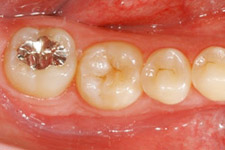

右:治療前の口腔内。

24歳、女性。右下第二大臼歯部(受容側)へ親知らず(ドナー歯)を移植してほしいという希望で来院されました。

ドナー歯はすでに歯根が完成しています。このような場合、移植後に歯髄(神経)の治療が必要です。